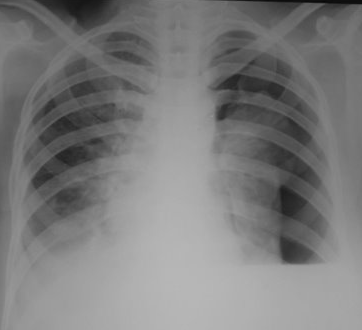

Rx toracică, incidență P-A

DESCRIERE:

DX: emfizem pulmonar

DD: